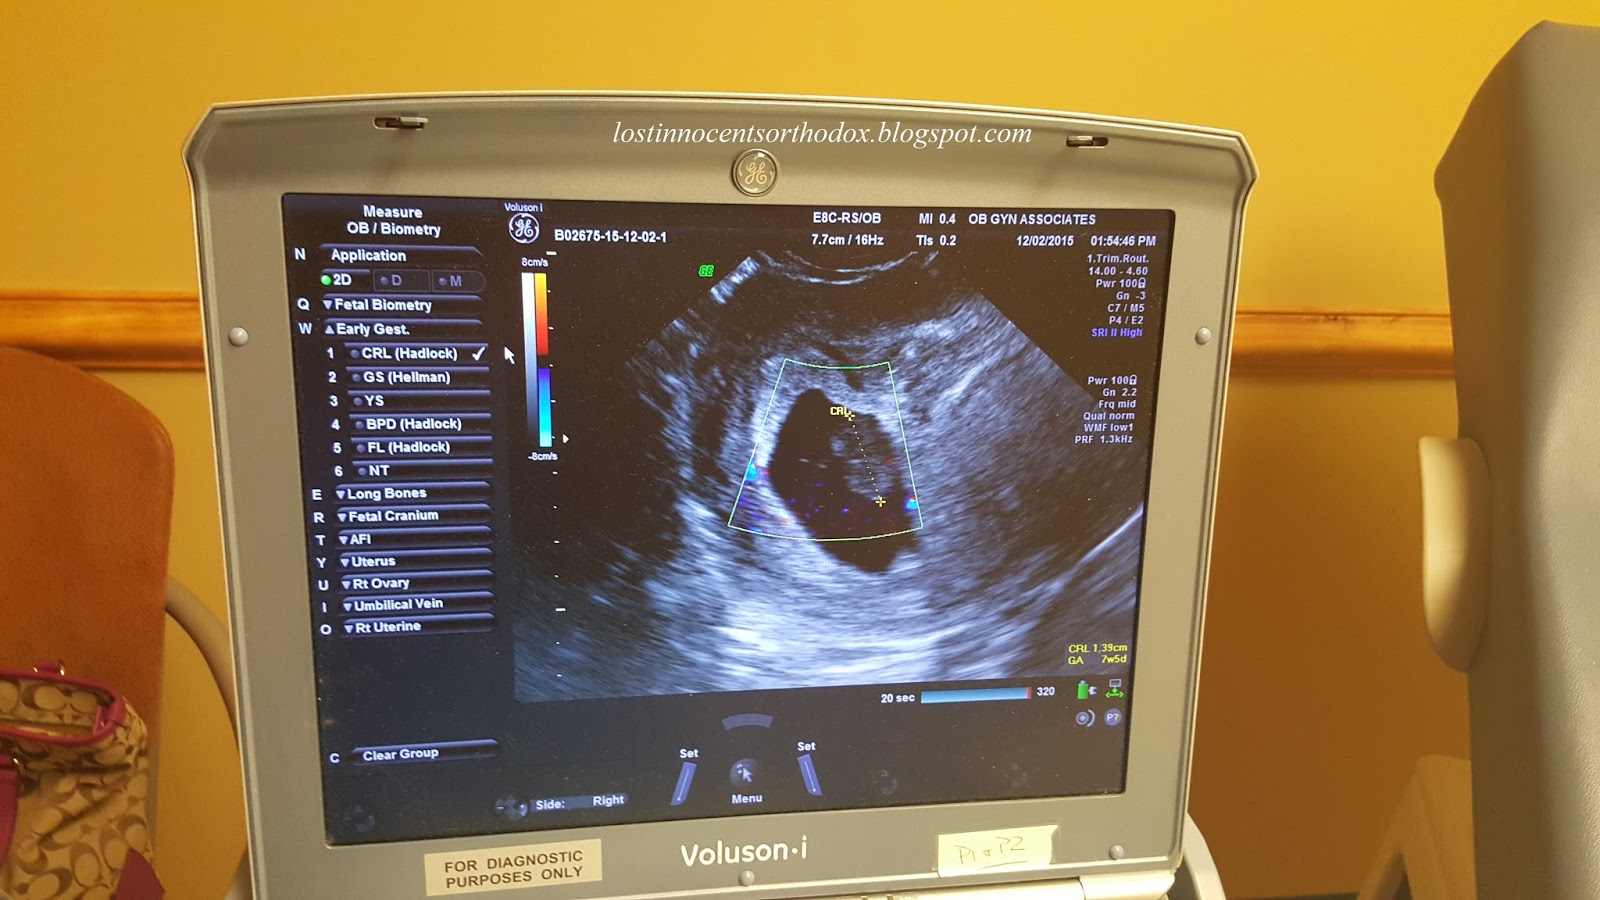

[Important note on recognizing the baby: Depending on how long it has been since the baby died, you may notice that the baby is smaller than you would expect for the age he/she was at death. Their size shrinks over time and so a baby who grew for eight weeks may only appear to be six to seven weeks at the time of delivery (or if another ultrasound is performed). This can be confusing to you. If, in fact, your baby died at six weeks but it is another few weeks before you deliver, you may not be able to see anything at all by the time you complete the miscarriage. Don’t feel that your baby never existed. As difficult as it is to experience, if you were pregnant, then you had a baby and you are that baby’s parent forever.